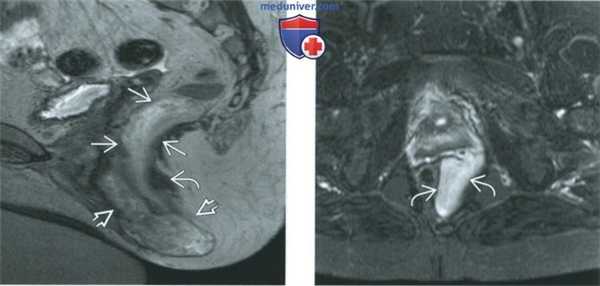

(Слева) При МРТ на Т2-ВИ FSE в аксиальной плоскости, центрированном на области вульвы, определяется относительно гиперинтенсивная дольчатая опухоль вульвы, растягивающая левую мышцу, поднимающую задний проход, и ее лобково-прямокишечную порцию. Исследование операционного материала выявило агрессивную ангиомиксому.

(Справа) При МРТ на Т1-ВИ FS в корональной плоскости с контрастированием агрессивная ангиомиксома имеет вытянутую форму и характеризуется усилением сигнала при введении контрастного вещества. Она прорастает мышцу, поднимающую задний проход, и распространяется на вульву, оттесняя при этом прямую кишку вправо. (Слева) При МРТ таза на Т1-ВИ FS в аксиальной плоскости с контрастированием определяется солидная опухоль правой боковой стенки таза, которая характеризуется значительным усилением сигнала и распространяется на влагалище и правую половину промежности, затрагивая также лобково-прямокишечную порцию мышцы, поднимающей задний проход. Исследование удаленной опухоли показало, что она является агрессивной ангиомиксомой.

(Справа) На субтракционном Т1-ВИ, полученном после введения контрастного вещества, в аксиальной плоскости на более низком уровне видно, что у той же пациентки агрессивная ангиомиксома прорастает мышцу, поднимающую задний проход, распространяясь на правую половину вульвы и правый свод влагалища.

(Слева) При МРТ на Т2-ВИ FSE в сагиттальной плоскости определяется гиперинтенсивная дольчатая опухоль таза, прорастающая мышцу, поднимающую задний проход. Опухоль имеет также массивный вульварный компонент. Исследование опухоли после ее хирургического удаления показало, что это агрессивная ангиомиксома.

(Справа) При МРТ на Т2-ВИ FS в аксиальной плоскости у пациентки с агрессивной ангиомиксомой в левой половине промежности визуализируется гиперинтенсивная солидная опухоль, располагающаяся на мышце, поднимающей задний проход.